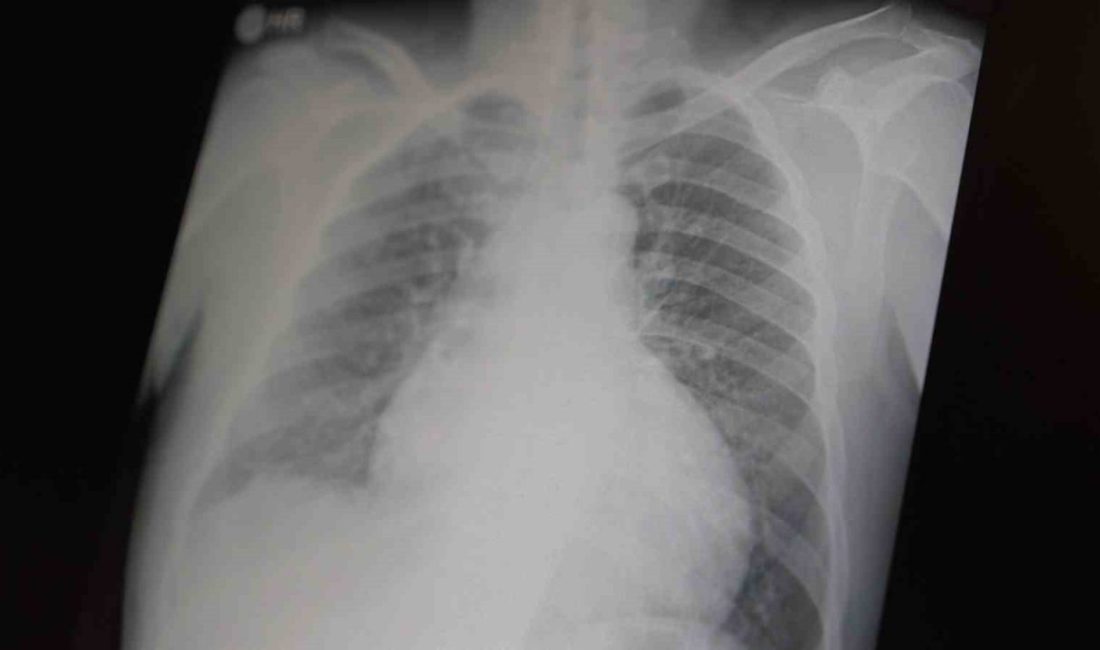

Prof. Dr. Şevket Özkaya, çocukları ve gençleri etkileyen bağımlılıklar hakkında açıklamalarda bulundu. Metamfetaminin sentetik bir uyuşturucu olduğunu ve kullanımının ölümcül sonuçlar doğurduğunu ifade eden Özkaya, “Tüm dünyada çocukları ve gençleri etkileyen iki önemli bağımlılıktan bahsetmek istiyorum. Bunlar metamfetamin ve kokain bağımlılığıdır. Metamfetamin en ölümcül, en çok bağımlılık yapan, okul çağında en kolay ulaşılabilen bir sentetik uyuşturucudur. Kullanıma bağlı ciddi akciğer ve karaciğer sorunları ortaya çıkıyor. Çok küçük dozlarda bile anında bağımlılık yapabiliyor ve tedaviyle bırakılması çok zor bir bağımlılıktır” dedi.

Açıklamalarında, her iki uyuşturucunun beyin hasarı oluşturduğunu ve nöro sinir hücrelerini harap ederek solunum ve kalbin durmasına sebep olduğunu vurgulayan Özkaya, “Metamfetamin tüm dünyada bir sorun olmanın ötesinde, ülkemizde de gençlerimizi etkileyen toplumsal bir sorun olarak görülmelidir” ifadelerini kullandı.